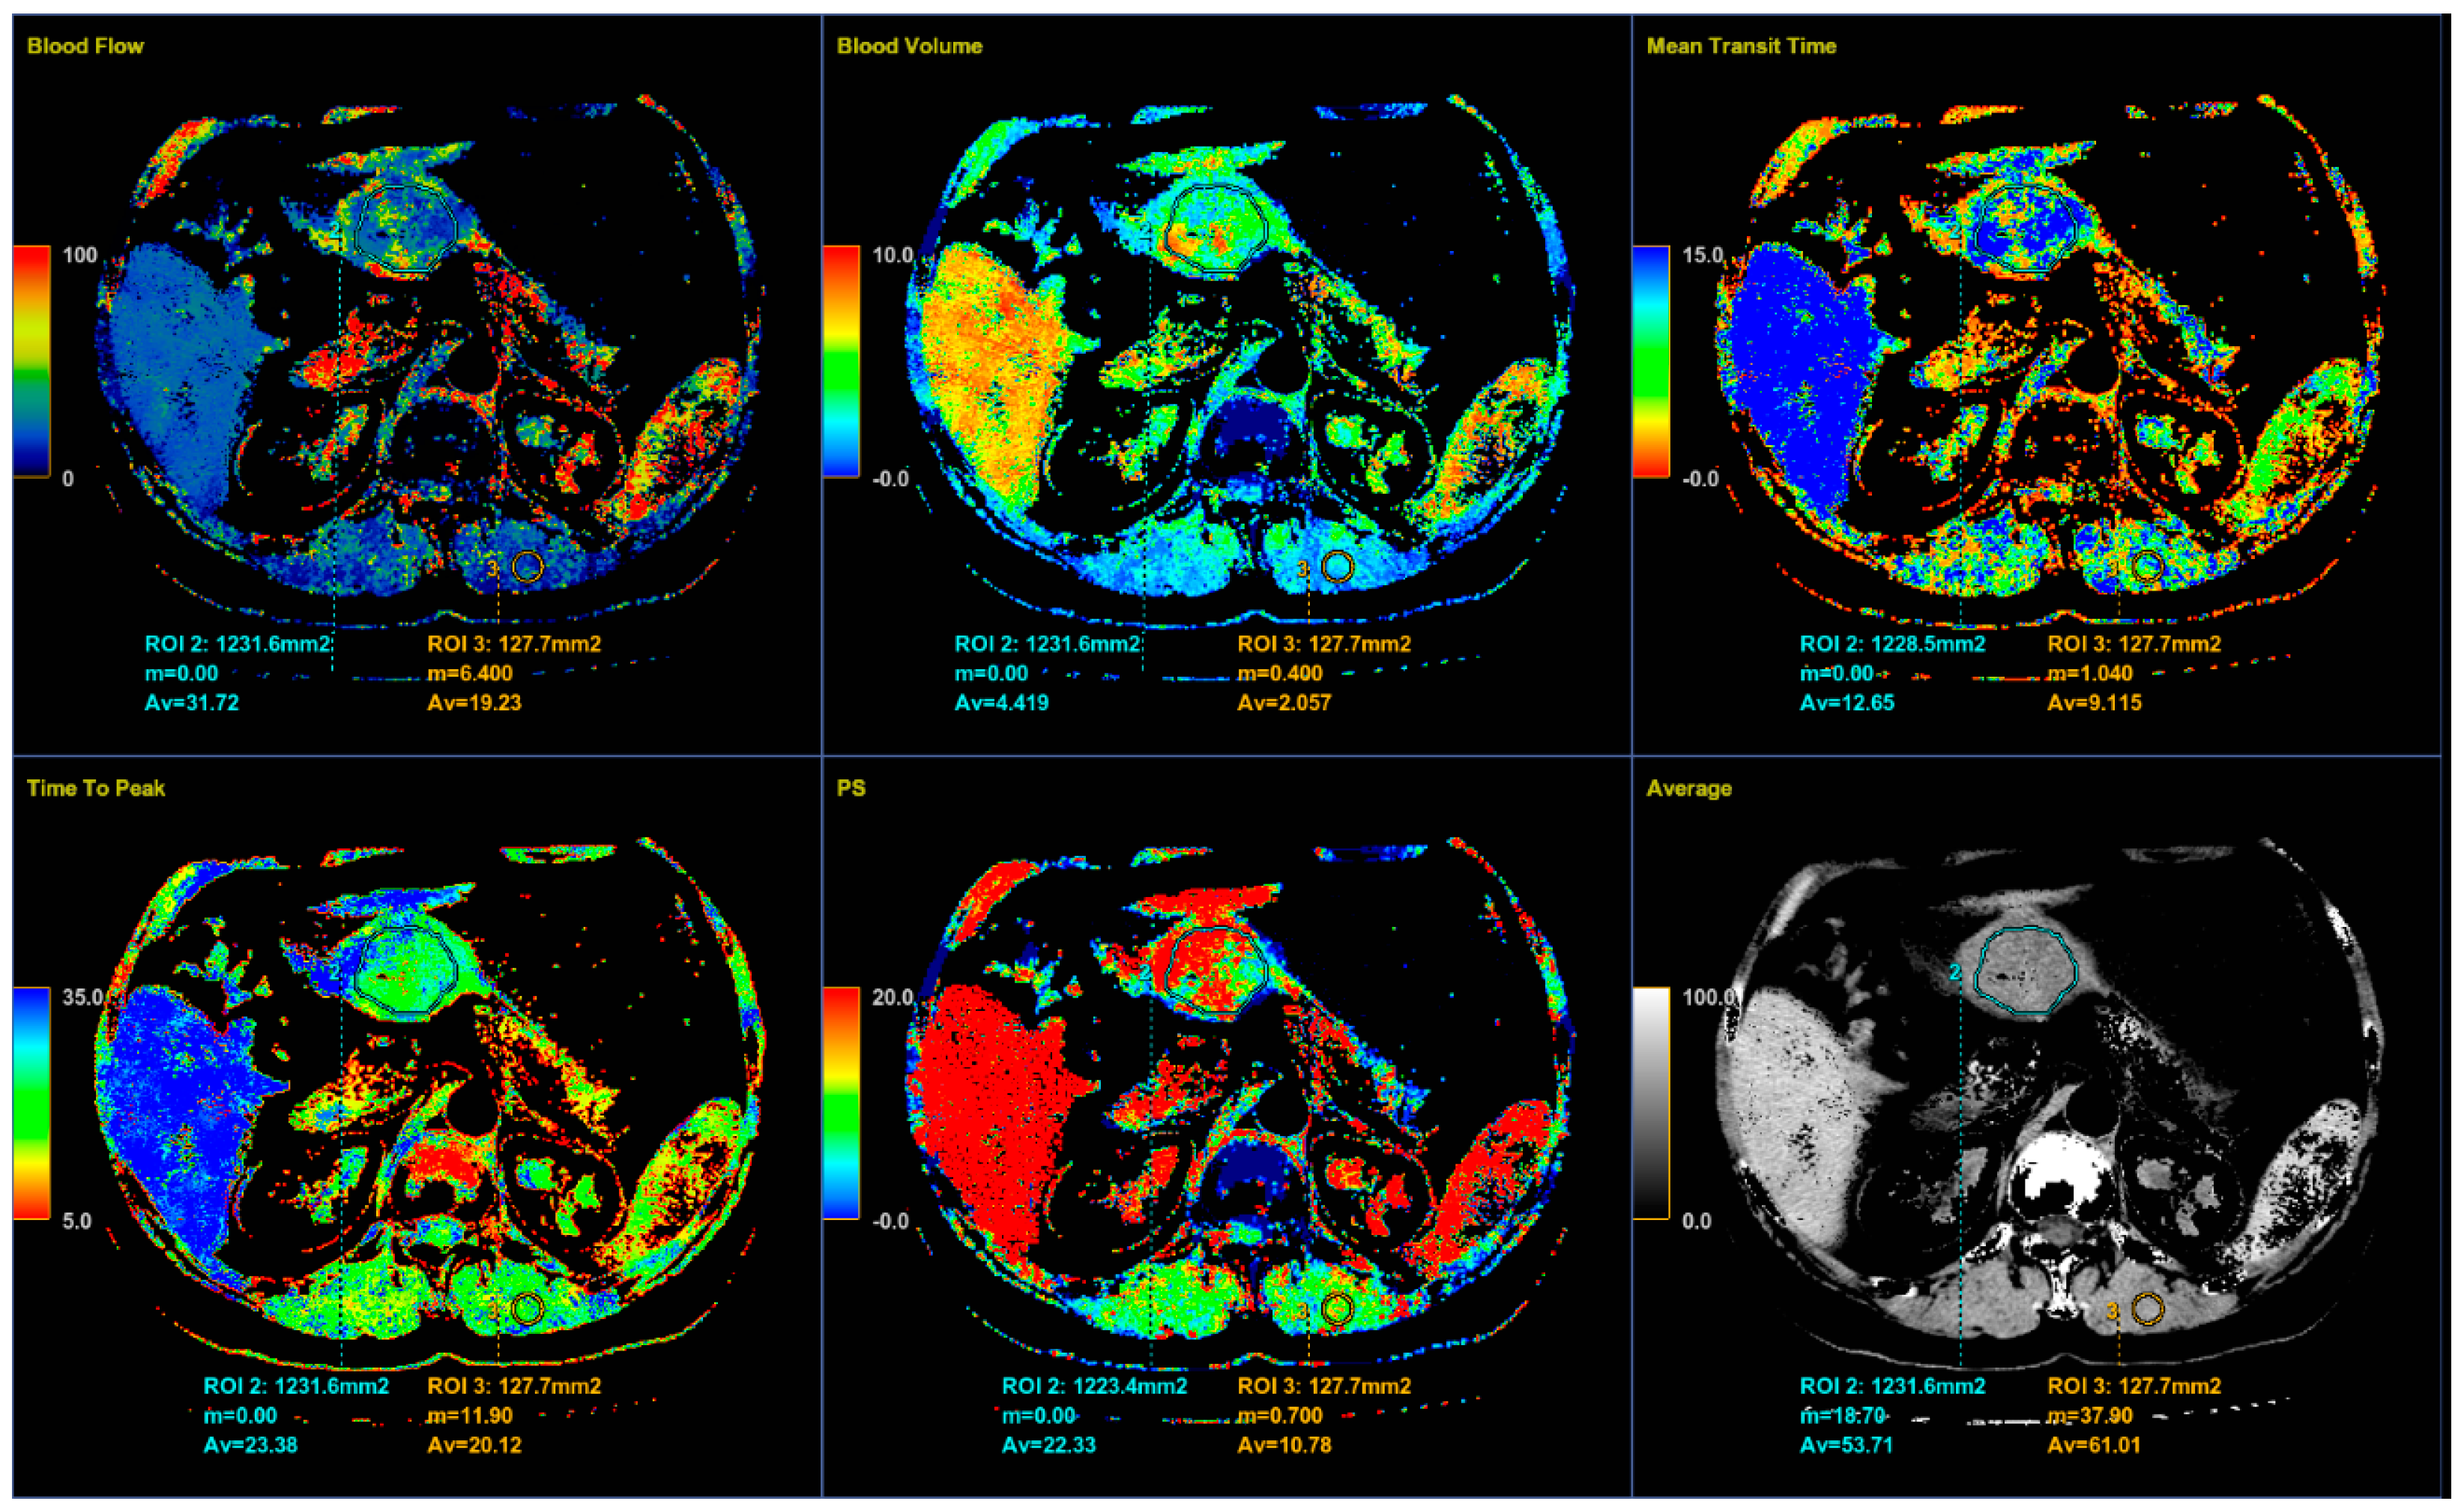

CT imaging features were analyzed as follows: maximal diameter in the axial slice and tumor structure, which was classified into cystic and solid/necrotic. The shape was depicted as regular or irregular. Tumor localization considered the body of the stomach, antrum or pyloric region. Mucosa was observed in two ways: intact/continuous or disrupted. Growth patterns were categorized as exophytic/mixed or endophytic. The degrees of enhancement of the solid part of tumor tissue were divided into weak, moderate or obvious enhancements. The presence of enlarged feeding or draining vessels (EFDV) was also recorded, as was the presence of metastasis in liver and other organs ( Figure 1, Figure 2 and Figure 3).

Perfusion CT data were analyzed by calculating perfusion according to the deconvolution method. The arterial input function was obtained from a 4–6 mm² circular region of interest (ROI) that was placed in the abdominal aorta. The arterial time-attenuation curve was derived automatically, and parametric colored maps were displayed for each of the four consecutive series of perfusion CT (Figure 4a). One radiologist placed a circular ROI as large as possible within the solid tumor region as well as in the nearby paravertebral skeletal muscles, taking care to avoid large vessels, at the reference and parametric images on each of the four consecutive slices (Figure 4b).

Color parametric maps of the following quantitative perfusion parameters have been automatically computed within these ROIs using the commercial software (Body Perfusion 4.0, GE Health-Care Technologies, USA): blood flow—BF (mL/min/100 g tissue); blood volume—BV (mL/100 g tissue); mean transit time—MTT (s); permeability surface area product—PS (mL/min/100 g tissue); and time to peak—TTP (s) (Figure 5). The values of the perfusion parameters of tumor were recorded for each section of gastric tumor ROI, and the same was done for muscle ROIs. Mean values of the perfusion parameters derived from the four consecutive sections were averaged and used for further analysis.

It is known that CT perfusion parameters may correlate with tumor risk. It was shown that poorly differentiated tumors have higher values of BF, BV and PS and shorter MTT than less aggressive tumors of the same type [13,25,26,27]. There are no available studies that have investigated the significance of CT perfusion in the preoperative prediction of the metastatic potential of gastric GISTs. Our results also show a tendency for higher values of perfusion parameters in highly aggressive gastric GISTs, as well as shorter MTT. However, there was no statistically significant difference except for PS and TTP. The velocity of inflow to the tumor microvasculature and capillary permeability proved to be the most reliable perfusion parameters for predicting the HR tumor with statistically significantly higher values in the group of HR GISTs, which was also confirmed by other perfusion studies on the different types of malignant tumors [26]. The TTP, indicating the time interval from the beginning of contrast administration to the peak attenuation of the tumor tissue, although a semi quantitative perfusion parameter showed a statistical significance in discriminating the HR from LR GISTs, which was proved by the univariate regression analysis. This result seems significant because there is no need for the commercial CT perfusion software to assess the TTP. The values of this perfusion parameter are available by simply reading from the time-attenuation curve of applied ROI in the CT perfusion series (Figure 4a, b), without complex calculations those are necessary for obtaining the other CT perfusion parameter values.

Figure 4. An 8-mm reconstructed image from the low-dose CT perfusion series of a 57-years old female patient with gastric GIST. Time-density curve on computed tomography perfusion (a). The arterial (yellow), tumor (blue), and muscle (orange), time-attenuation curves of the corresponding CT perfusion section. A freehand ROI (this tool measures area in square milimeters) in the region of tumor and round ROIs in the aorta and paravertebral muscle (b).